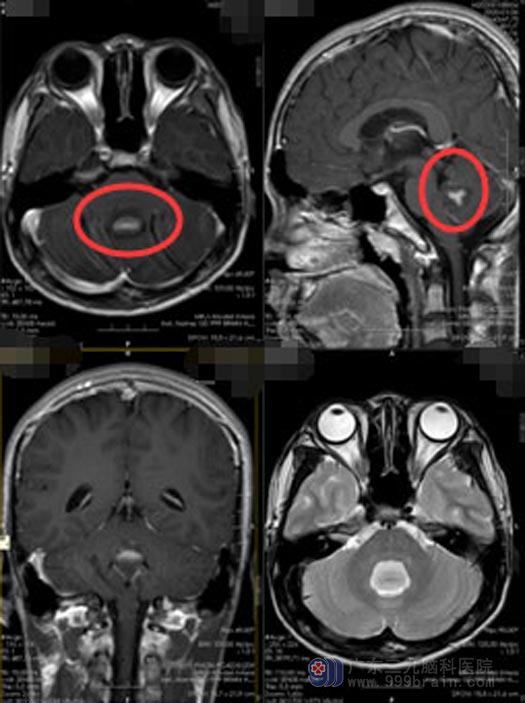

神经外五科主任鲁明接诊后,仔细检查了铭铭的影像资料,四脑室区偏下方占位性病变,考虑为髓母细胞瘤可能性大。ASL示:四脑室占位性病变DWI序列呈高信号,ASL呈稍低灌注。

为明确病情,结合铭铭的病史、临床症状及影像表现,鲁明邀请了肿瘤科医生进行联合会诊。经过讨论分析、鲁明建议术前辅助局部放疗,减少肿瘤负荷后再行下一步治疗。经过9Gy/5f术前放疗后,铭铭的头痛、呕吐的情况好转。放疗结束,手术指征明确,完善相关检查后,神经外五科团队携手为铭铭在全麻下行“四脑室占位性病变切除术+左顶枕硬膜下血肿钻孔引流术”,手术过程顺利。